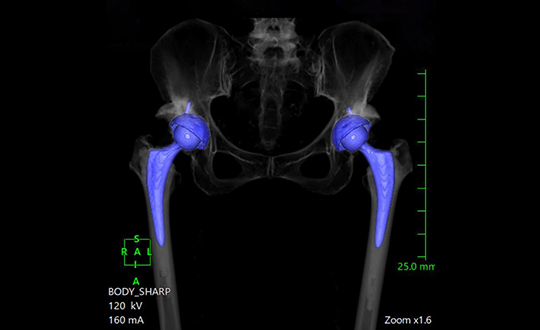

人工股関節置換術は、傷んだ股関節の軟骨・骨を取り除き、骨盤側に人工の受け皿(カップ)、大腿骨側に人工の軸(ステム)と骨頭を入れて関節を置き換える手術です。痛みの原因となる関節面を人工物に置き換えることで、強い痛みを大きく軽減し、歩行や日常生活動作を改善することを目的とします。